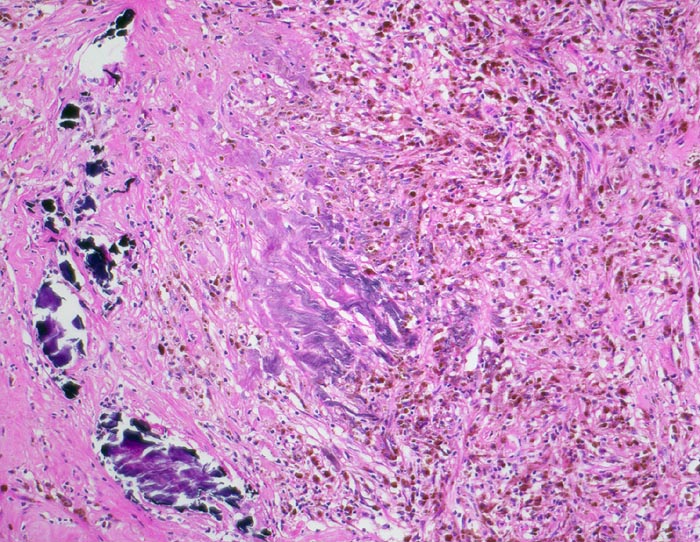

hellzelliges Nierenzellkarzinom: Stromaverkalkungen und Einblutungen

Sklerosiertes Stroma mit grobscholligen dystrophen Verkalkungen und Blutungsresiduen in Form von hämosiderinbeladenen Makrophagen (braune Zellen in der rechten Bildhälfte).

8cm grosser Tumor im Nierenoberpol. Bunte Schnittfläche mit multiplen gelben Knoten, ödematösem Stroma und Einblutungen, sowie fokaler Zystenbildung. Der Tumor infiltriert das Nierenbecken. Die Vena renalis ist tumorfrei.

Wiederholte schmerzhafte Makrohämaturie. Im Urin werden Karzinomzellen nachgewiesen. Sonographisch und im Abdomen CT kommt ein Tumor im rechten Nierenoberpol zur Darstellung. Der Patient wird nephrektomiert.